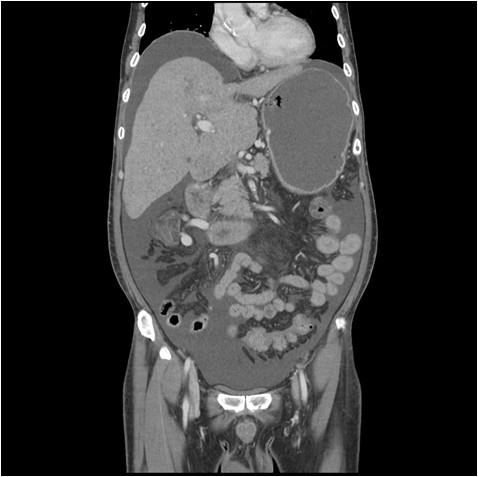

다운로드.jpg (이미지출처:능곡하나내과) 이 정도면 아주 심각하죠.

2018년도의 일입니다. 응급으로 들어온 환자가 제게 배정되었습니다. 나이도 나랑 동갑인데 열 살은 더 들어 보이는 환자분이 다리 열상(裂傷)으로 오셨지요. 마취 전 평가를 위해 훑어보다 보니 헤모글로빈도 낮아서 빈혈이 심하고 혈소판 수치도 정상보다 한참이나 낮았습니다. 이런 경우 십중팔구 간의 이상이라 짐작했습니다.

과거병력으로, 살아오는 동안 특별히 눈에 띄는 증상이 없어 검진은 안 받으며 지냈고 밥은 안 먹어도 소주는 반드시 1병을 마신 세월로 미루어 볼 때, 추정컨대 간경화(간경변)로 들어선 게 분명합니다.